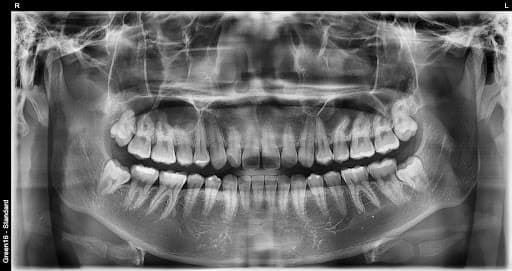

Past xavf

Oddiy aql tishi

Normal o'sgan aql tishi ham parvarish qilish qiyin bo'lgani uchun karies xavfi yuqori